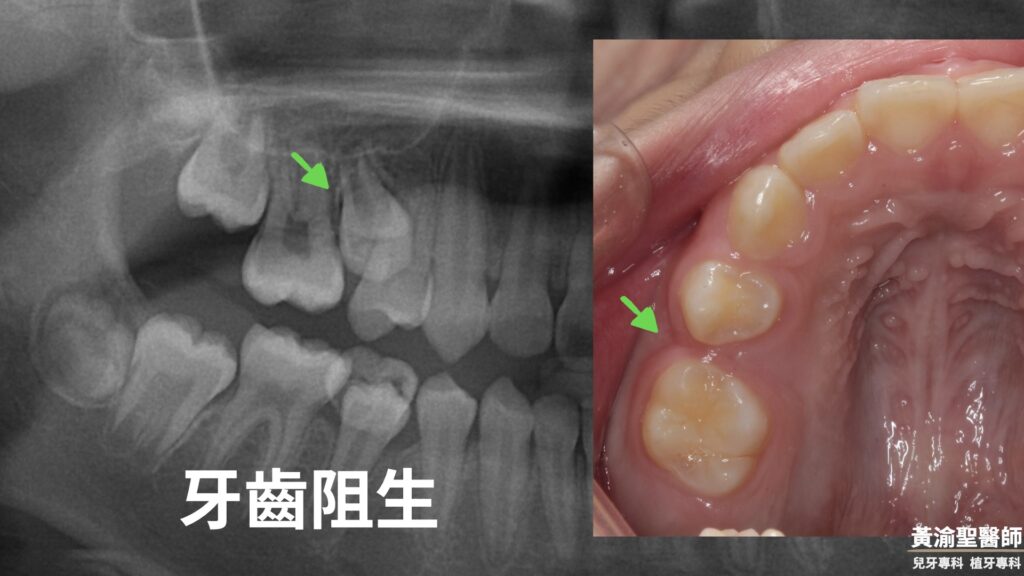

在診所拍x光發現

第二小臼齒卡住出不來

可以看到術前術後

第二小臼齒順利長出來了